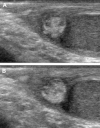

Scrotal trauma accounts for less than 1% of all trauma-related injuries. Traumatic injuries of the epididymis are extremely rare.Here we report a rare case of hematoma of the epididymis, diagnosed with US, in a 10-year-old boy after a sport injury.